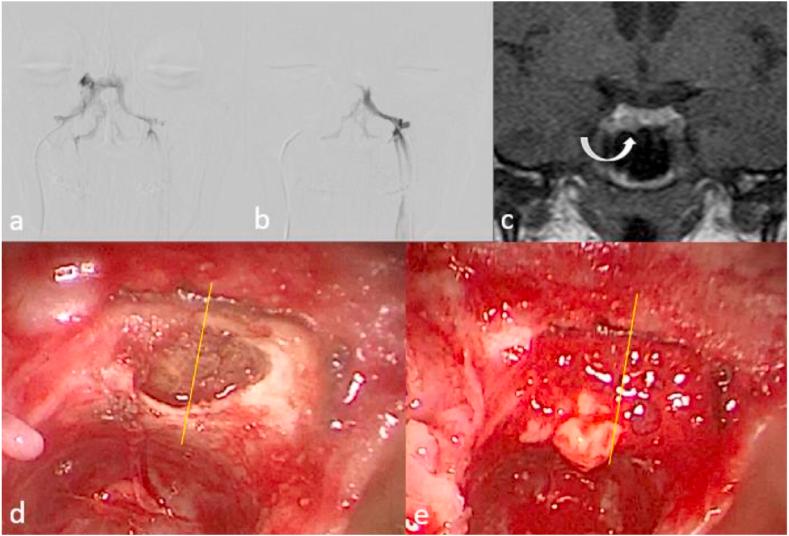

Inferior petrosal sinus sampling (IPSS) is known as the gold standard to distinguish whether excessive adrenocorticotropin hormone (ACTH) production origins from the pituitary gland or an ectopic source. However, due to a number of factors, the value of IPSS for adenoma lateralization may be limited. Aim of this study was to evaluate the influence of parasellar venous drainage (VD) patterns on IPSS findings in predicting lateralization of pituitary microadenomas.

Seventeen patients with pathologically confirmed Cushing's disease were retrospectively reviewed. The median age of the included patients was 37 years. Laterality of parasellar VD perfectly associated with lateralization as measured by IPSS. Symmetrical VD was associated with symmetrical ACTH gradient on IPSS. However, lateralization measured by IPSS did not show any significant correlation with lateralization detected during ETSS.

Our study suggests that IPSS lateralization results strongly depend on parasellar VD pattern but show no significant correlation with the adenoma lateralization found during ETSS. Thus, IPSS does not appear to be an appropriate modality to predict adenoma lateralization.

岩下窦采血(IPSS)是区分促肾上腺皮质激素(ACTH)过度分泌源于垂体还是异位来源的金标准。然而,由于多种因素,IPSS在腺瘤定位方面的价值可能有限。本研究的目的是评估鞍旁静脉引流(VD)模式对IPSS结果在预测垂体微腺瘤定位中的影响。

回顾性分析了17例经病理证实的库欣病患者。纳入患者的中位年龄为37岁。鞍旁VD的侧别与IPSS测量的侧别完全相关。对称的VD与IPSS上的对称ACTH梯度相关。然而,IPSS测量的侧别与ETSS期间检测到的侧别无显著相关性。

我们的研究表明,IPSS侧别结果强烈依赖于鞍旁VD模式,但与ETSS期间发现的腺瘤侧别无显著相关性。因此,IPSS似乎不是预测腺瘤侧别的合适方法。